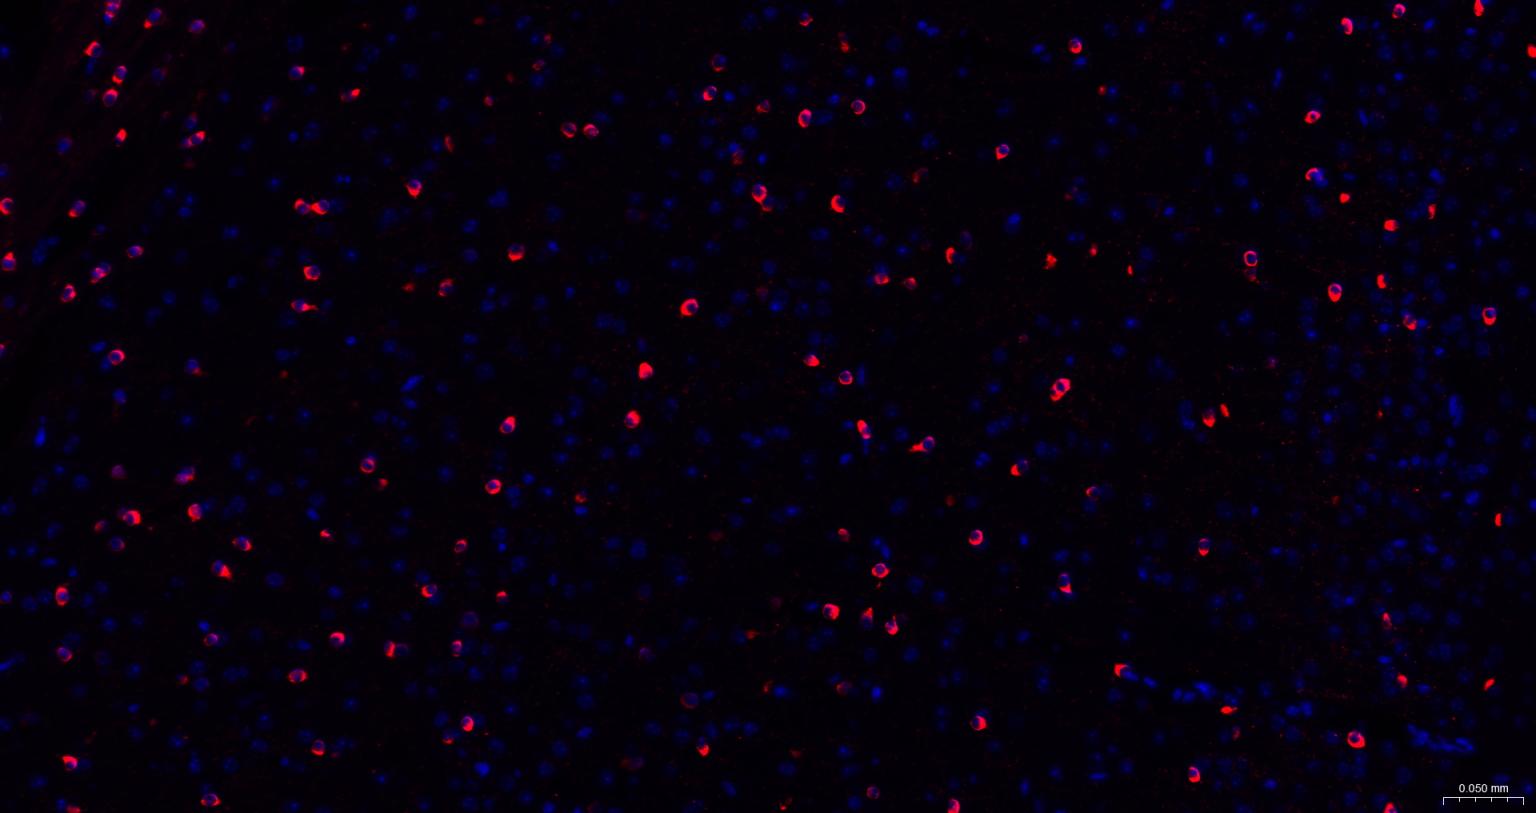

神经细胞标志物

(NMDAR1)N-甲基-D-天门冬氨酸受体(NMDAR)是兴奋性氨基酸受体亚型之一,是由NMDAR1与不同的NMDAR2亚基组成的异聚体。

The protein encoded by this gene is a critical subunit of N-methyl-D-aspartate receptors, members of the glutamate receptor channel superfamily which are heteromeric protein complexes with multiple subunits arranged to form a ligand-gated ion channel. These subunits play a key role in the plasticity of synapses, which is believed to underlie memory and learning. Cell-specific factors are thought to control expression of different isoforms, possibly contributing to the functional diversity of the subunits. Alternatively spliced transcript variants have been described. [provided by RefSeq, Jul 2008]

| IF | Human, Mouse, Rat | 1:100-500 |